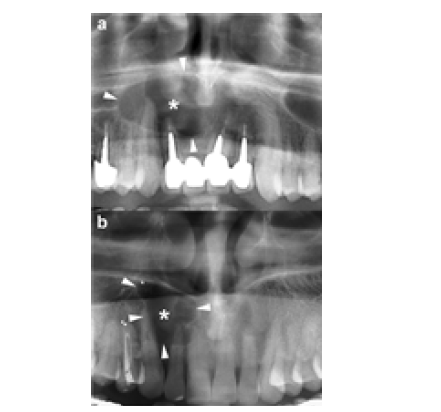

A cropped panoramic radiograph reveals a large OKC with well-defined, lobulated borders (arrowheads) occupying the mandibular body. An incomplete internal septum is also visible within the lesion (opposing arrows). Approximately 30% of OKCs are associated with at least one unerupted tooth-most commonly the third molars [9]. This association is observed more frequently in younger patients [15]. The radiographic characteristics of OKCs are not pathognomonic, especially in small unilocular lesions [15]. When a small unilocular OKC appears in the anterior maxillary sextant, it may mimic other odontogenic or non-odontogenic cysts, such as radicular cysts (Figure 1), lateral periodontal cysts or nasopalatine duct cysts [17]. Histologically confirmed OKCs. Cropped panoramic radiographs (a and b) demonstrate two unilocular radiolucent lesions (asterisks) with well-defined, corticated borders (arrowheads) located in the anterior maxilla between the roots of adjacent teeth. The radiographic appearance of these radiolucencies may mimic a radicular cyst. Large mandibular OKCs characteristically grow along the length of the mandible, showing minimal Bucco-lingual expansion, particularly within the mandibular body [15]. On panoramic radiography, this growth pattern typically presents as an extensive radiolucent lesion with significant mesiodistal extension and little or no cortical expansion (Figure 1 & 2). In contrast, large maxillary OKCs often produce marked expansion of the alveolar bone and may involve adjacent anatomical structures. Notably, when a maxillary OKC originates in the molar region, extension into the maxillary sinus is commonly observed (Figure 2) [22].

Figure 3:a) Panoramic radiograph • Shows a large radiolucent area in the maxilla. • The lesion has a well-defined, corticated rim, which typically indicates a slow-growing process. • The white arrows (in the original figure) point to the margins of the cystic lesion. b) Axial MDCT - bone window This view highlights bony structures. • Shows hydraulic (balloon-like) expansion of the maxillary alveolar bone. • Black arrows originally indicate the direction of this expansion. • Wavy arrows show thinning of the buccal cortical plate. • Curved arrows identify focal perforation of the buccal cortex.

Similar to panoramic radiography, CT scan depicts the main radiological characteristics of OKCs, including size, shape (hydraulic or scalloped), margins (well-defined and corticated), internal configuration (uni- or multilocular) and effects on adjacent structures such as displacement of teeth, root resorption, elevation of the maxillary sinus floor or inferior displacement of the mandibular canal. Additionally, CT provides valuable information on other features of OKCs, including buccolingual or palatal expansion, cortical erosion, internal density and soft tissue extension (Figure 3a & 3b).

a. Panoramic radiograph

• Shows a large radiolucent area in the maxilla.

• The lesion has a well-defined, corticated rim, which

typically indicates a slow-growing process.

• The white arrows (in the original figure) point to the

margins of the cystic lesion.

b. Axial MDCT - bone window

This view highlights bony structures.

• Shows hydraulic (balloon-like) expansion of the maxillary

alveolar bone.

• Black arrows originally indicate the direction of this

expansion.

• Wavy arrows show thinning of the buccal cortical plate.

• Curved arrows identify focal perforation of the buccal

cortex.

These features are common with OKCs due to their tendency to grow anteroposteriorly and expand bone with minimal buccolingual widening-though expansion can still occur in maxillary lesions.

c. Axial MDCT - soft tissue window

Highlights soft tissue differences.

• Shows posterior bowing of the maxillary sinus floor, often

caused by mass effect from the lesion (arrowheads).

• Asterisks denote inflammatory contents within the left

maxillary sinus, which may occur secondarily from obstruction or

irritation caused by the lesion.